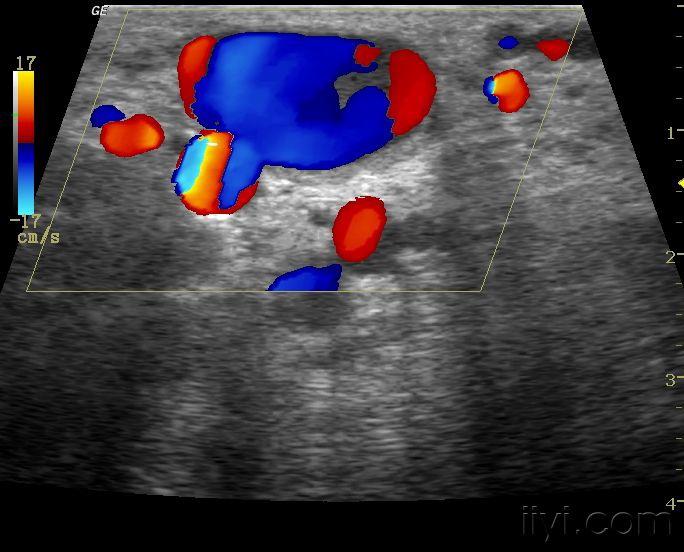

动静脉瘘 - 超声医学讨论版 - 爱爱医医学论坛